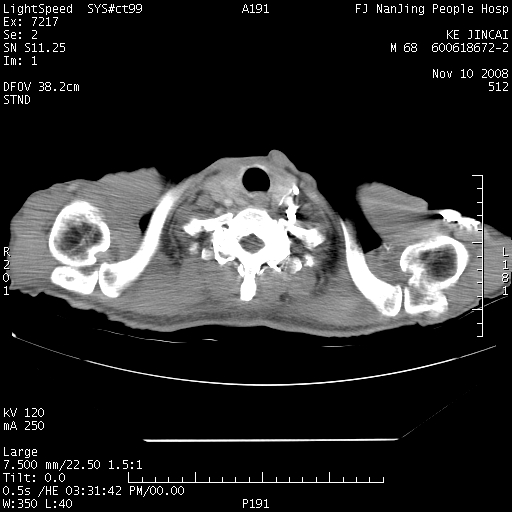

是个很有看头的病例,咋人气那么不旺?没多少人兴趣呢?这个病例几大怪:1   恶性肿瘤侵犯心肌左房怪,心肌一般不会被恶性肿瘤侵犯吧?2   左下肺均匀实变怪,内无含气,有别一般不张实变,含气肺泡完全为液体取代,而非一般不张实变的肺萎陷,冷不丁还以为是肿大的脾脏3   肿瘤本身怪,像tb肺不张4   这么有看头的病例没人气怪。呵呵。

左肺恶性肿瘤侵犯肺动脉,左心房内瘤栓,胸膜转移。

左肺恶性肿瘤侵犯肺动脉,左心房内瘤栓,胸膜转移,少见,学习了。